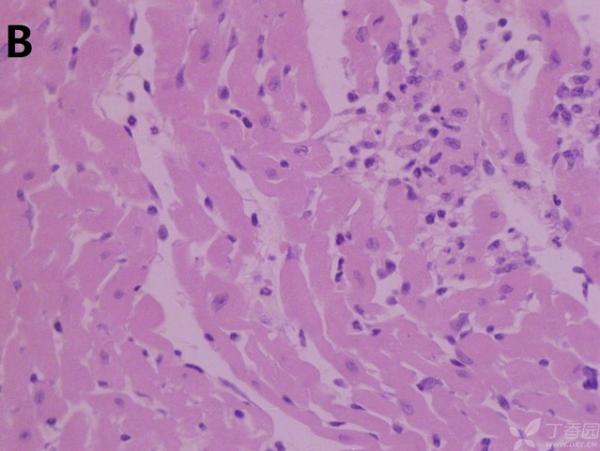

ÎÒ½«Ã¿¸ö×éÖ¯ÅÄÁË3¸öÊÓÒ°£¬ÒÔ±ã×ۺϷÖÎö£¬Âé·³¸÷λ°ïÎÒ°ÑA¡¢B¡¢C¡¢D¡¢E¡¢F¡¢GµÄËðÉË´óСÅŸö˳Ðò ÔÙ°ÑA¡¢B¡¢C¡¢H¡¢I¡¢JËðÉ˵ÄÑÏÖØ³Ì¶ÈÅŸöÐò¡£¸ÃÎÊÌâÒ²ÔÚ¶¡ÏãÔ°ÉÏÇóÖúÁË£¬Á´½Óhttp://www.dxy.cn/bbs/topic/23986562 A1.jpg A2.jpg A3.jpg B1.jpg B2.jpg B3.jpg C1.jpg C2.jpg C3.jpg D1.jpg D2.jpg D3.jpg E.jpg F1.jpg F2.jpg F3.jpg G1.jpg G2.jpg G3.jpg H1.jpg H2.jpg I.jpg I2.jpg I3.jpg J.jpg J2.jpg J3.jpg [ Last edited by ÀëÈËÏæÑÅÀá on 2012-10-9 at 21:11 ] |